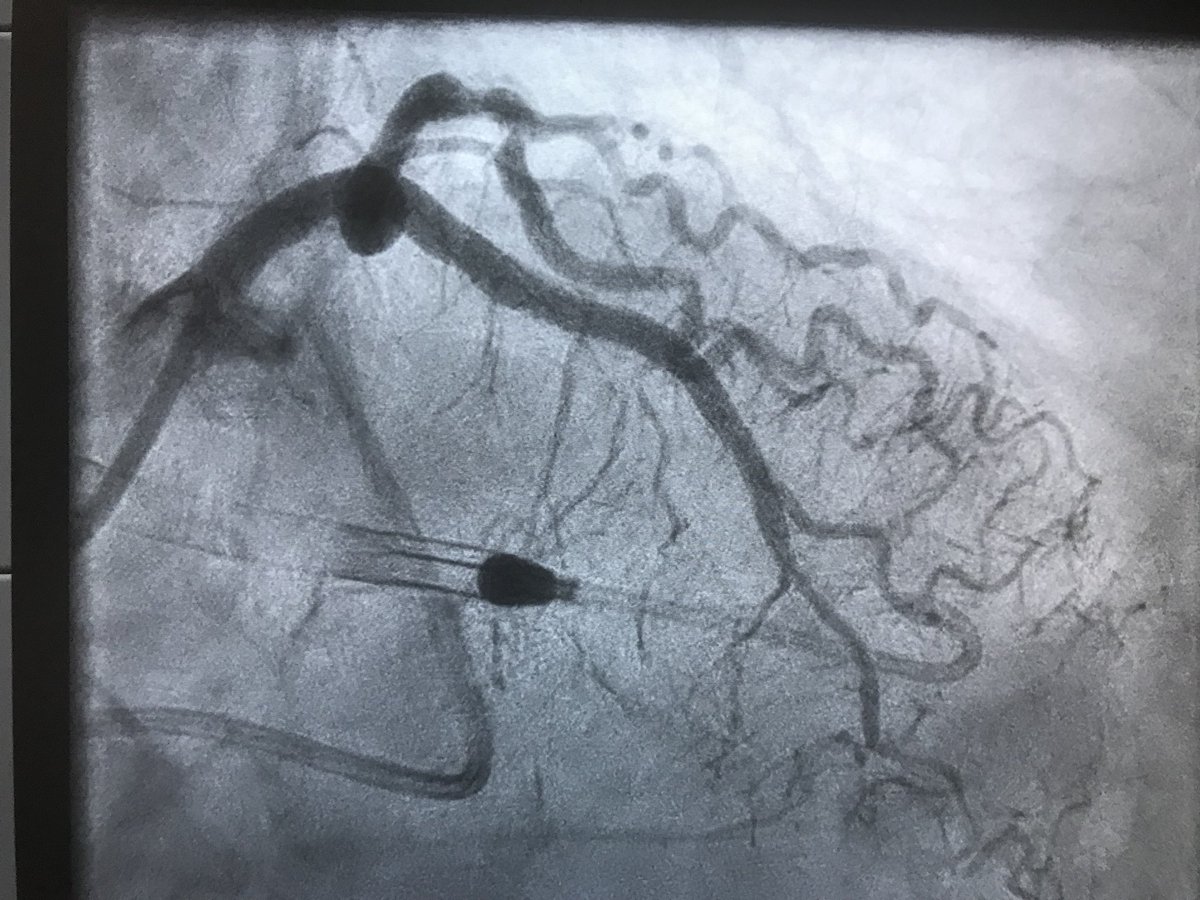

Then went #PercAx for heavily calcified LM in cardiogenic shock after we were unable to get catheters up from right and left radial, right femoral…and finding this gem in the left iliac

RajTayalMD's tweet image. Then went #PercAx for heavily calcified LM in cardiogenic shock after we were unable to get catheters up from right and left radial, right femoral…and finding this gem in the left iliac